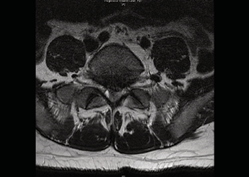

Lumbar spine magnetic resonance imaging (MRI) elicited severe spinal canal stenosis at the S1 level secondary to posterior protrusion of a degenerative L5/S1 disc (Figure1,2).

Figure 2: Axial T2 weighted MRI at the level of L5/S1 showing extruded disc (from L5/S1) causing central compression of the thecal sac at the S1 level just after the S1 nerve roots have lateralized.

There was loss of cerebrospinal fluid signal surrounding the cauda equina fibres consistent with cauda equina compression.